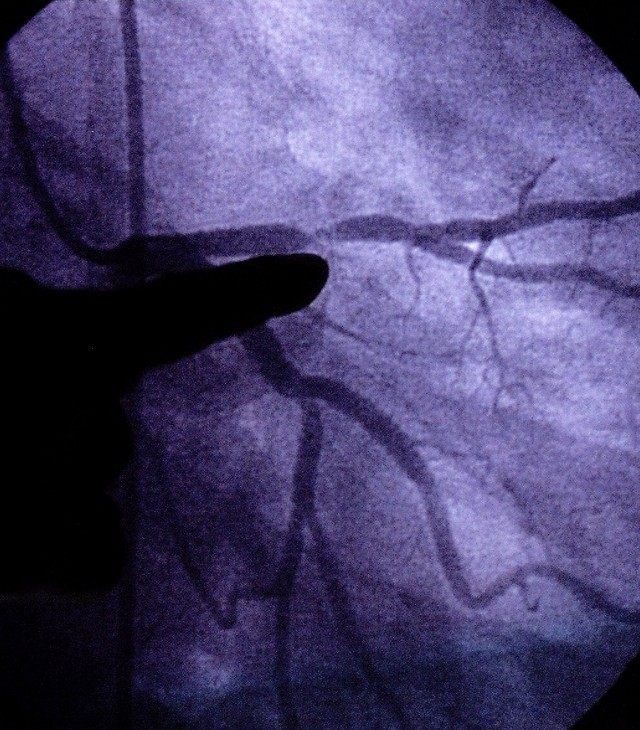

First, researchers verified that stature played a role: The risk of coronary artery disease — clogged arteries — rose 13.5 percent with each 6.5 centimeter (about 2.5 inches) decrease in height.

One theory for the disadvantage is that short people have smaller arteries, so it may take less plaque to clog them. But researchers say this can’t be the whole explanation. Women have smaller arteries than men, yet when the study results were analyzed by gender, height was clearly linked to heart risks only in men. However, there were fewer women in the study with heart problems, so this could have made it tough to spot a possible effect.